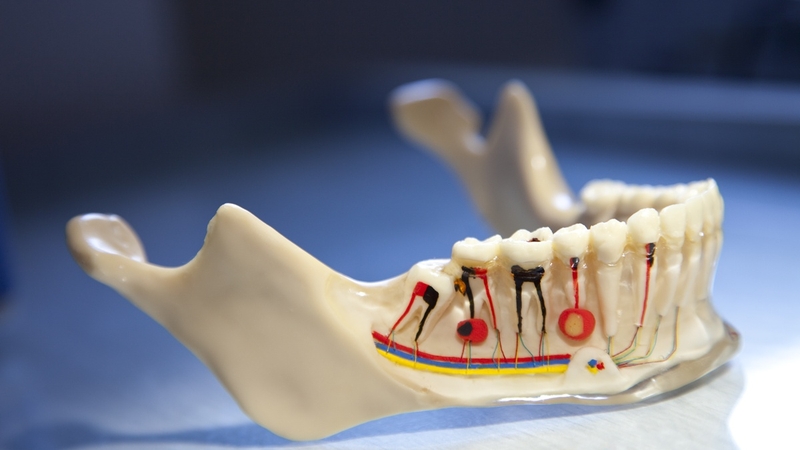

Phần tận cùng của chân răng được gọi là chóp răng, bắt đầu từ vị trí men-xê măng, nơi mà thân răng tiếp giáp với chân răng, kéo dài đến điểm cuối của chân răng. Khu vực này rất quan trọng do có lỗ chóp, cho phép sự lưu thông của mạch máu và dây thần kinh vào và ra khỏi hệ thống ống tủy.

Lỗ chóp là điểm kết nối giữa buồng tủy răng (nơi chứa tủy răng là các mô mềm sống) và các mô cũng như cấu trúc xương xung quanh. Kết nối này rất quan trọng cho việc cung cấp dinh dưỡng cho răng, vì các mạch máu, dây thần kinh đi qua lỗ chóp chịu trách nhiệm cung cấp cho tủy các chất dinh dưỡng cần thiết, oxy và thông tin cảm giác.

Hình dạng, kích thước của chóp răng có thể thay đổi tùy thuộc vào từng loại răng và vị trí của nó trong cung hàm. Răng cửa, nằm ở phía trước miệng, thường có chóp nhọn và thon gọn, còn răng hàm phía sau thường có chóp răng tròn hoặc ngắn hơn. Kích thước của chóp răng cũng bị ảnh hưởng bởi các yếu tố như tuổi tác, tình trạng sức khỏe của răng và các lần điều trị nha khoa trước đó.

Trong lĩnh vực nha khoa, chóp răng đóng vai trò quan trọng, đặc biệt trong các quy trình như điều trị tủy và đặt implant. Trong điều trị tủy, nha sĩ cần xác định và làm sạch chính xác chóp răng để loại bỏ hoàn toàn bất kỳ mô tủy bị nhiễm trùng hoặc viêm, đồng thời tạo điều kiện cho việc bịt kín đúng cách hệ thống ống tủy. Việc xác định và xử lý chính xác các vấn đề ở chóp răng là điều cần thiết cho sự thành công của điều trị tủy và sức khỏe lâu dài của răng.

Trong quá trình cấy ghép implant răng, vị trí chóp răng và sự liên kết với xương xung quanh là yếu tố quan trọng để xác định vị trí và góc đặt implant phù hợp. Với mục đích đảm bảo rằng việc đặt implant diễn ra an toàn, đạt hiệu quả cao, nha sĩ cần đánh giá cẩn thận cấu trúc giải phẫu của chóp răng và lượng xương hiện có.